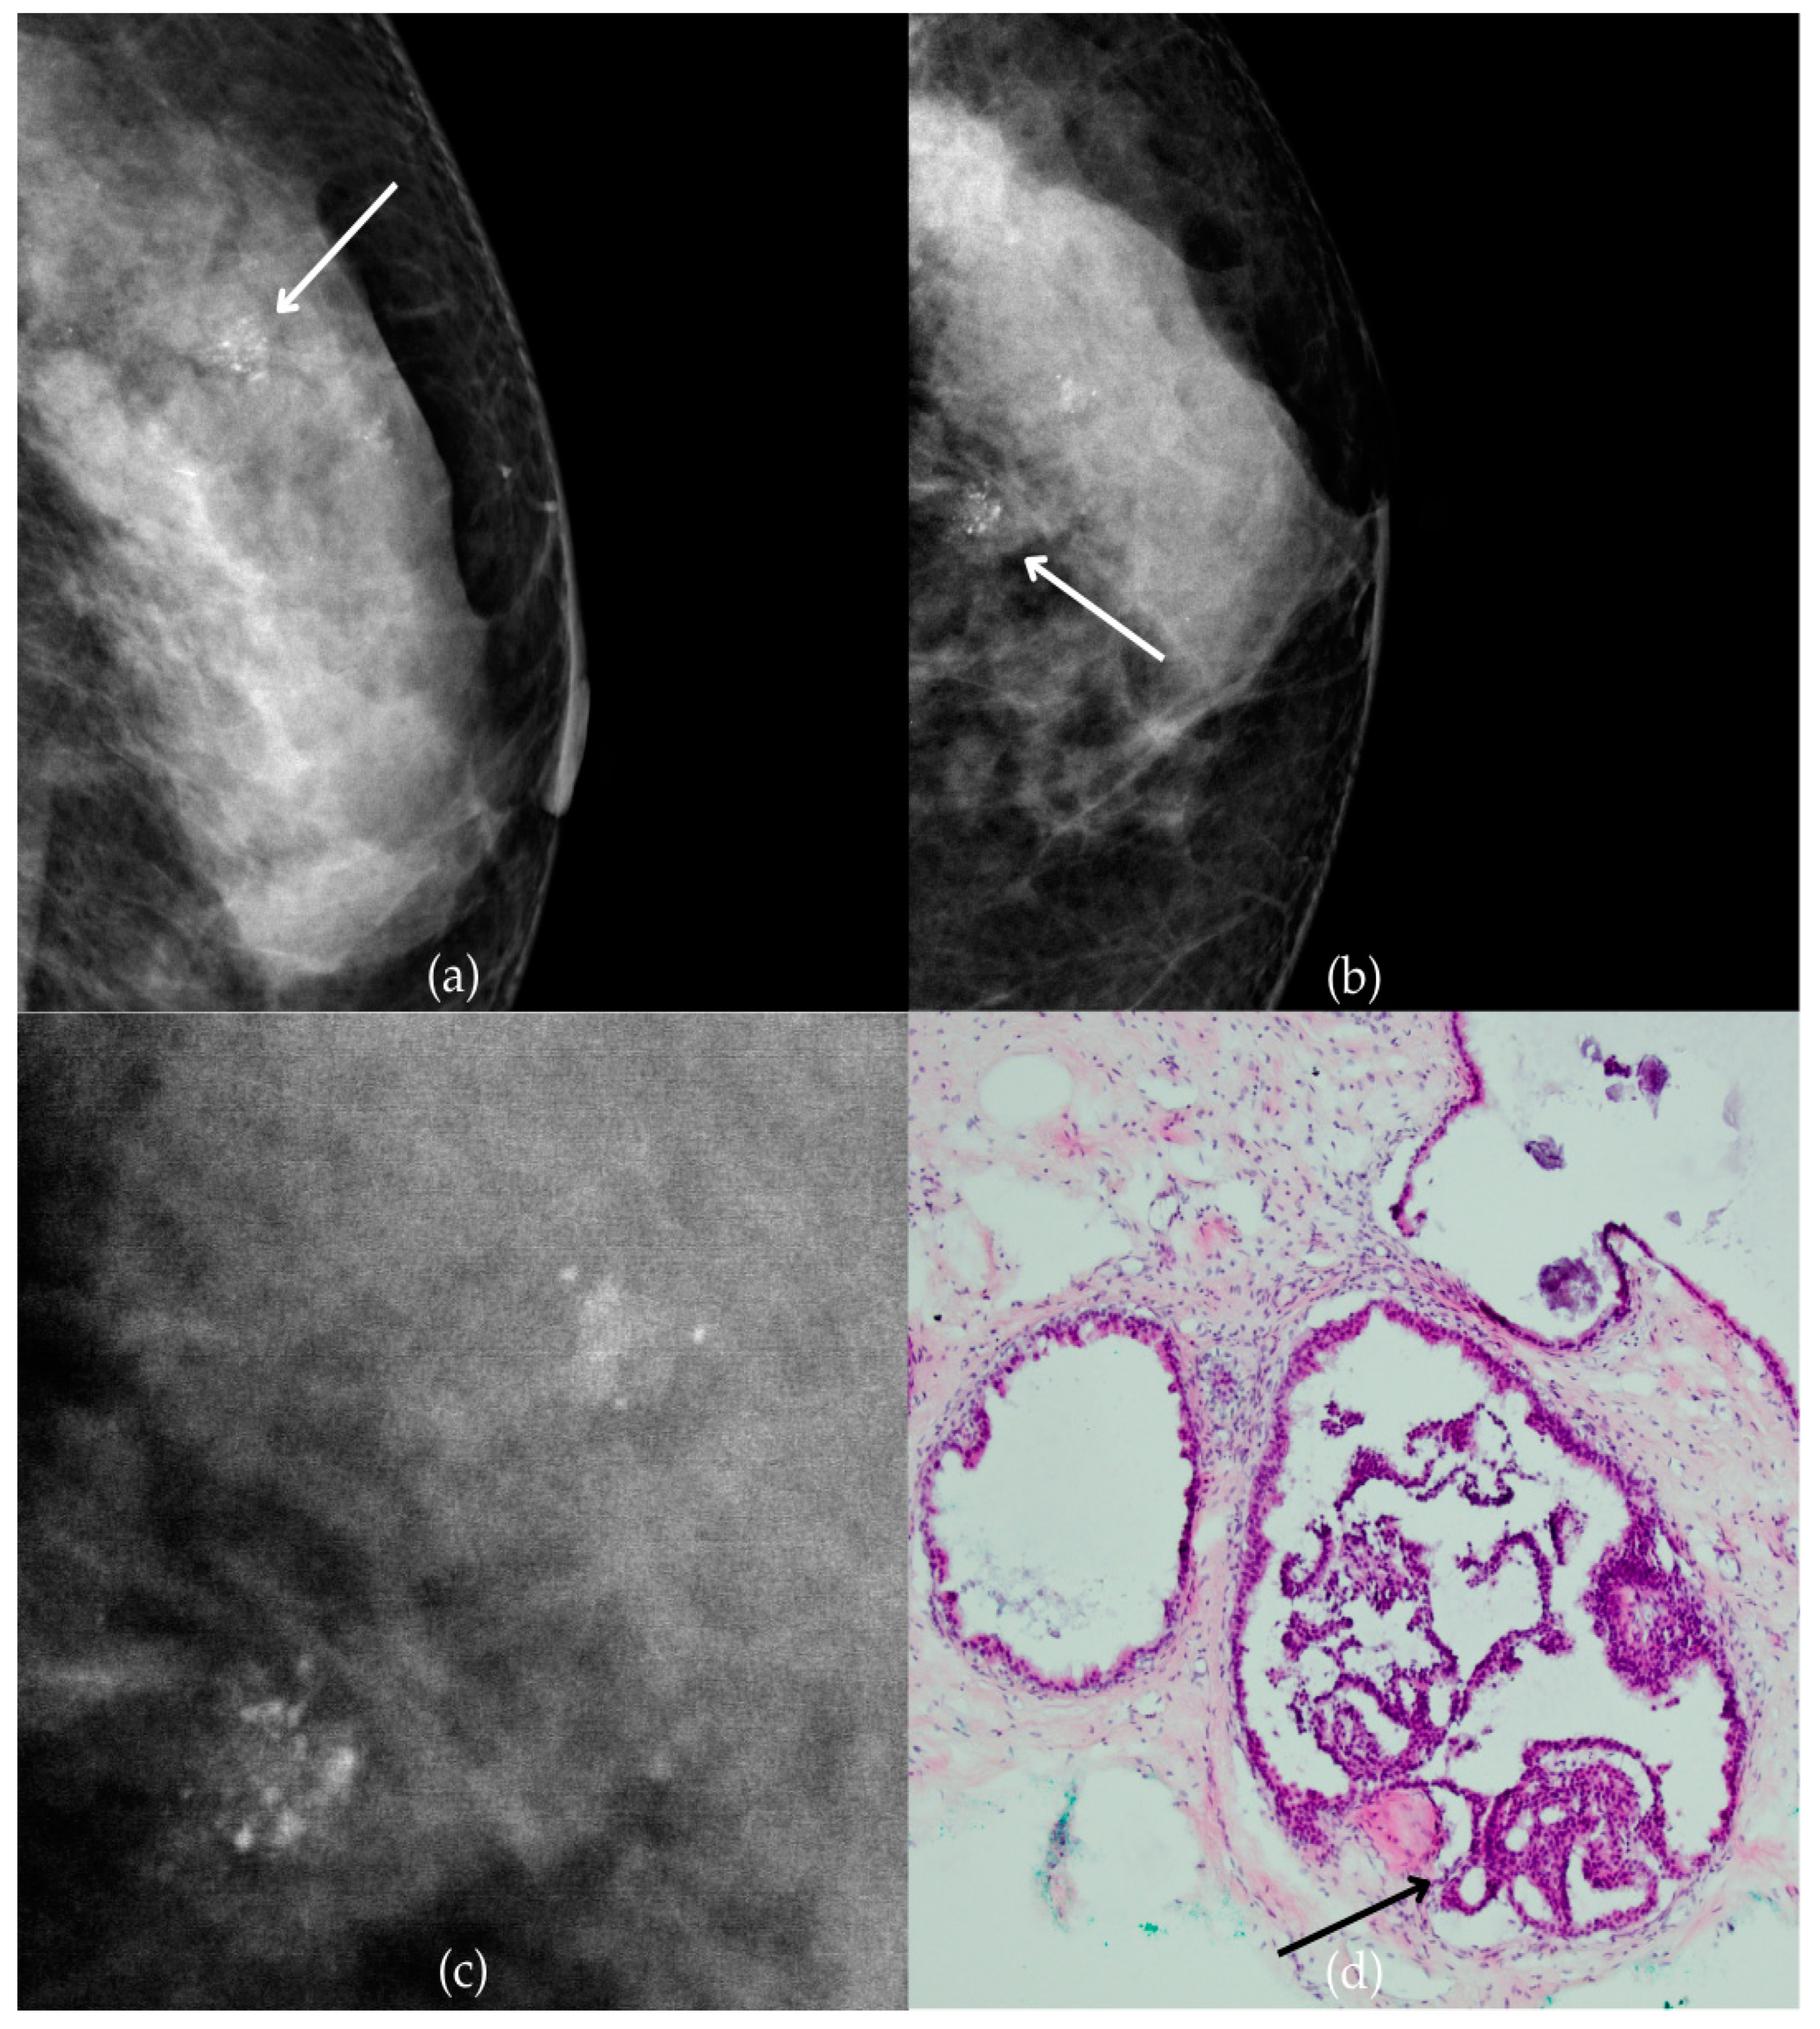

The mammogram and histopathological images (Figure 4) of the 62-year-old patient’s left breast show grouped coarse heterogeneous calcifications in the upper outer quadrant, corresponding to a BI-RADS 3 finding. Tissue analysis obtained through biopsy indicated the presence of an invasive carcinoma (category B5b). The patient underwent quadrantectomy, and postoperative pathology confirmed the diagnosis of invasive carcinoma. The patient’s most recent MRI, performed two years after the initial diagnosis, was assessed as BI-RADS 2, suggesting benign changes.

Figure 4.

Invasive breast cancer. (a) Mediolateral oblique (MLO) mammography view; (b) craniocaudal (CC) mammography view of the left breast showing grouped coarse heterogeneous calcifications (marked with arrows) in the upper outer quadrant. (c) Magnified mammographic image of grouped coarse heterogeneous calcifications. (d) The histopathological image of the biopsy sample shows the characteristic features of invasive cancer (marked with arrow) and ductal carcinoma in situ (DCIS) (marked with arrowhead) (HE staining; 40× magnification).